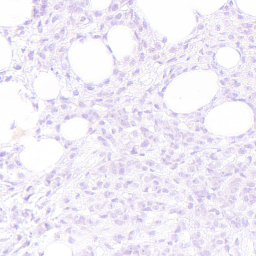

Refer to captionRefer to captionRefer to captionRefer to captionRefer to captionRefer to captionRefer to captionRefer to captionRefer to captionRefer to captionRefer to captionRefer to captionRefer to captionRefer to captionRefer to captionRefer to captionRefer to captionRefer to captionRefer to captionRefer to captionRefer to captionRefer to captionRefer to captionRefer to captionRefer to captionRefer to captionRefer to captionRefer to captionRefer to captionRefer to captionRefer to captionRefer to captionRefer to captionRefer to captionRefer to captionRefer to captionRefer to captionRefer to captionRefer to captionRefer to captionRefer to captionRefer to captionRefer to captionRefer to captionRefer to captionRefer to captionRefer to captionRefer to captionRefer to captionRefer to captionRefer to captionStyle Transfer [6]Ours (Nearby Style Cond.)Ours (Multi-Patch Style Cond.)StylesStylesStyles (selection, 3 of 10)LayoutsLayoutsLayouts

Figure 4: Image generation results with the HER2 dataset, for the style transfer baseline [6] (left), our proposed method trained with nearby patches as style source (center) and our proposed method trained with multi-patches as style source (right). Note that white represents tumor tissue in the layout images, while black includes all background structures.

Figures 4 and 5 show examples of generated images for the HER2 and CATCH dataset. The style transfer baseline [6] captures some of the staining characteristics for the HER2 dataset, but also creates some darker blurred areas, which are not commonly seen in HER2 images. On the CATCH dataset, the global color scheme is transferred to the synthetic images, but no delineation between tumor and background area is visible. For our method the generated images adhere to the spatial layout and also represent the styles in the query images for both the nearby and multi-patch configuration, even though the query images were not seen during training.